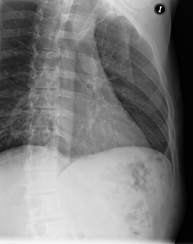

- Tórax

- RX Tórax

Técnica mediante la cual, utilizando rayos X, se obtienen imágenes de la caja torácica (corazón, pulmones, arcos costales, clavículas, etc.) para su estudio. - RX Esternón

- Chest X-ray

A chest X-ray uses a small dose of radiation to obtain a two-dimensional image of the thoracic cavity and its contents (lungs, heart, mediastinum, etc.). It is one of the most commonly performed medical tests.